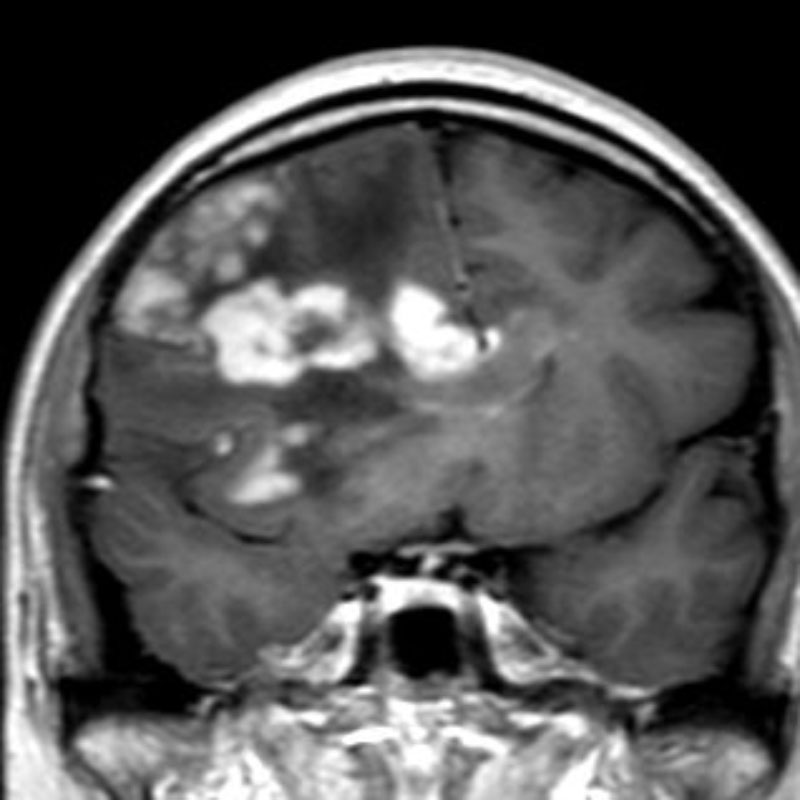

360

'22年12月

70代

右前頭葉膠芽腫

頭蓋内腫瘍摘出術

No.’22_117 手術前1

No.’22_117 手術前2